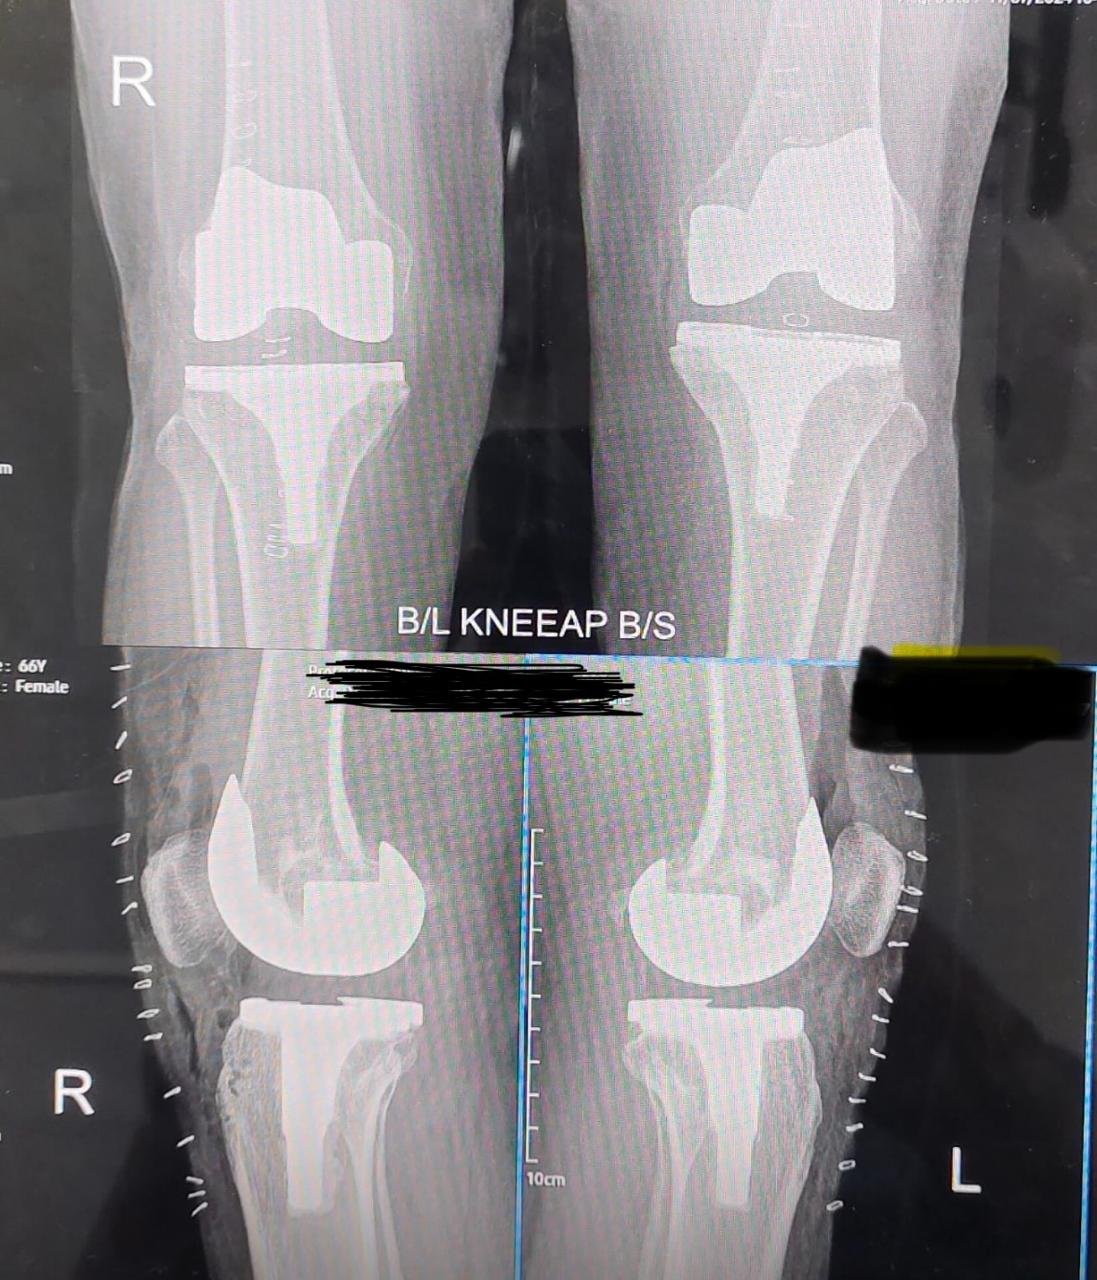

Post OP X-Ray after Implantation

Post-Operative X-Ray After Implantation is performed to evaluate the accurate positioning and alignment of the implanted device following surgery. This imaging helps surgeons confirm implant stability, assess bone integration, and identify any immediate post-surgical complications. It plays a crucial role in ensuring successful surgical outcomes and guiding further rehabilitation or follow-up treatment planning.